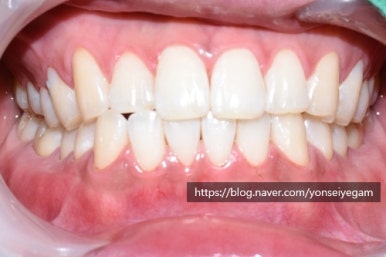

커피를 많이 드신다는 직장인 남자분인데요

1일1커피 또는 그이상하는 분들 많으시죠?

담배를 피지 않음에도 치아가 아래 사진과 같은 모습이었어요.

치료 전 모습으로 치아가 누렇고 착색이 있으며, 치아 패인 부분이 있음(화살표)

구강검진 후 스케일링,치아 패인곳(화살표) 떼우기, 원데이2회미백을 진행하기로 상담하였으며